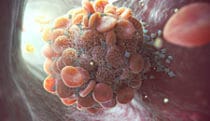

The tumor microenvironment